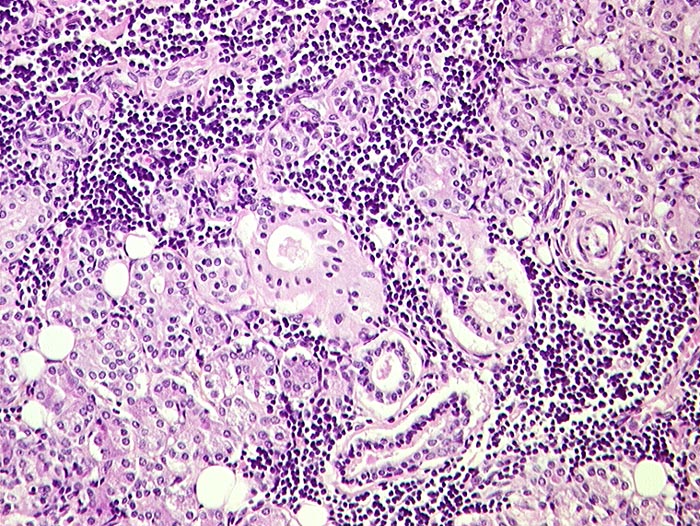

Autoimmun- Sialadenitis bei Sjögren Syndrom

Parotis

Das Zellbild ist je nach Stadium mehr oder weniger zellreich und zusammengesetzt aus Lymphozyten, Myoepithelien und selten Azinuszellen. Ein lymphozytäres Zellbild ist in Kombination mit dem typischen klinischen Bild (Keratokonjunktivitis sicca, Xerostomie, rheumatische Erkrankung) für die Sicherung der Diagnose ausreichend. Auf die Lippenbiopsie kann in diesem Fall verzichtet werden.